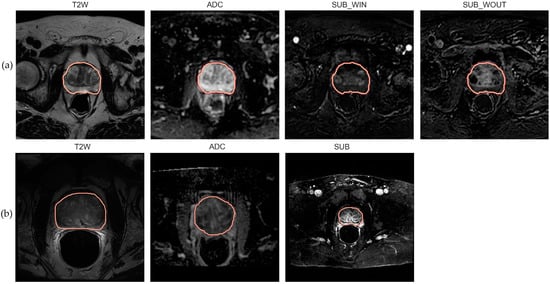

We processed DWI and DCE sequences to generate the Apparent Diffusion Coefficient (ADC) and subtraction (SUB) maps. We derived the ADC map by computing the negative gradient associated with a least-square fit (straight line) over the DWI acquisitions with three b-values—0, 1500, and 2000 mm/s2. We processed the DCE acquisitions to generate two subtraction (SUB) maps describing the wash-in (SUBwin) and wash-out (SUBwout) phases of the contrast agent. The maps were computed by splitting the DCE acquisitions at a time point close to 90s in the temporal domain, i.e., SUBwin = DCE90+ε-DCE0 and SUBwout = DCEt_n-DCE90+ε. This was performed to capture the contrast agent inflow (wash-in) and outflow (wash-out) phases which are known to guide radiologists in assessing the malignancy in PCa management [42]. Here, t_n indicates the last DCE acquisition in the temporal domain. ε represents the deviation from the referenced time point. Table 1a presents a simplified summary of the internal dataset properties, and Figure 1, panel (a) highlights mid-gland level axial mpMRI slices of a sample patient from the population.

Figure 1.

Mid-level axial slice of the prostate gland with ROI annotation. (a) T2w, ADC, SUBwin, and SUBwout images associated with a random patient sampled from the internal population; (b) T2w, ADC, and SUB images associated with a random patient sampled from the external population.

The in-built scanner software generated ADC and DCE SUB maps. The SUB map was computed as the difference between the phases involved in contrast bolus arrival to the baseline. Ultimately manual segmentation of the whole prostate gland (amongst other ROIs) was performed by an experienced radiologist for each sequence and was included in the dataset. Table 1b presents a simplified summary of the external dataset properties, and Figure 1, panel (b), highlights mid-gland level axial mpMRI slices of a sample patient from the population.